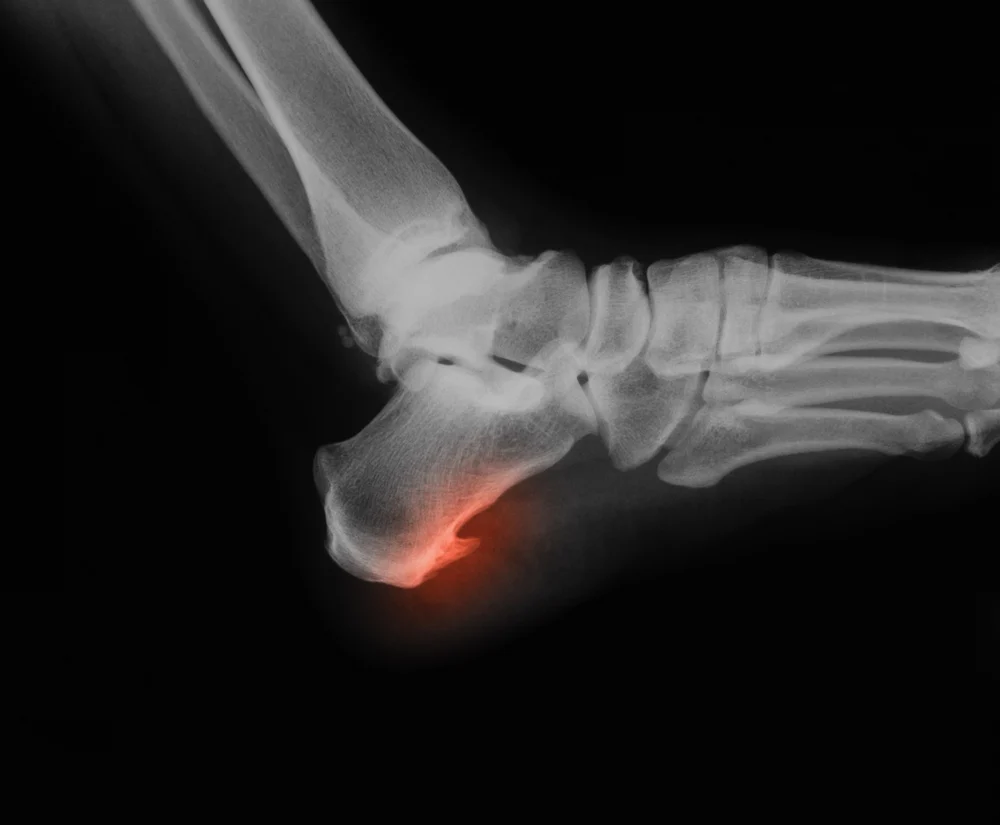

کفی طبی آماده یا سفارشی برای خار پاشنه؟

خار پاشنه: وقتی گام های زندگی دوباره لذت بخش می شوند